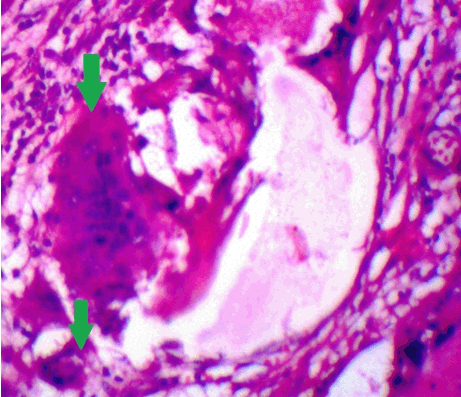

The clinical diagnosis in all the cases was suggestive of epidermoid/dermoid cyst. However, subsequent histopathologic examination confirmed these cases as pilomatricoma. All the lesions were well encapsulated. H&E sections showed dual population of cells comprising the peripheral basaloid cells and the ghost or shadow cells in the centre (Figure 1). A transition of basaloid to ghost cells was noted in many areas. Sections from the right eyebrow swelling posed great difficulty in diagnosis since there were mainly ghost cells present and almost negligible basophilic cells representing stage 4 (Figure 2). The remaining four cases (80%) belonged to the third morphological stage. Two cases showed a rich infiltrate of lymphoplasmacytic cells and numerous foreign body giant cells near the shadow cells (Figure 3). Three cases showed areas of calcification.

Figure 2: Ghost cells with keratinization (▲). Basophilic cells are almost absent (H&E stain, x400).